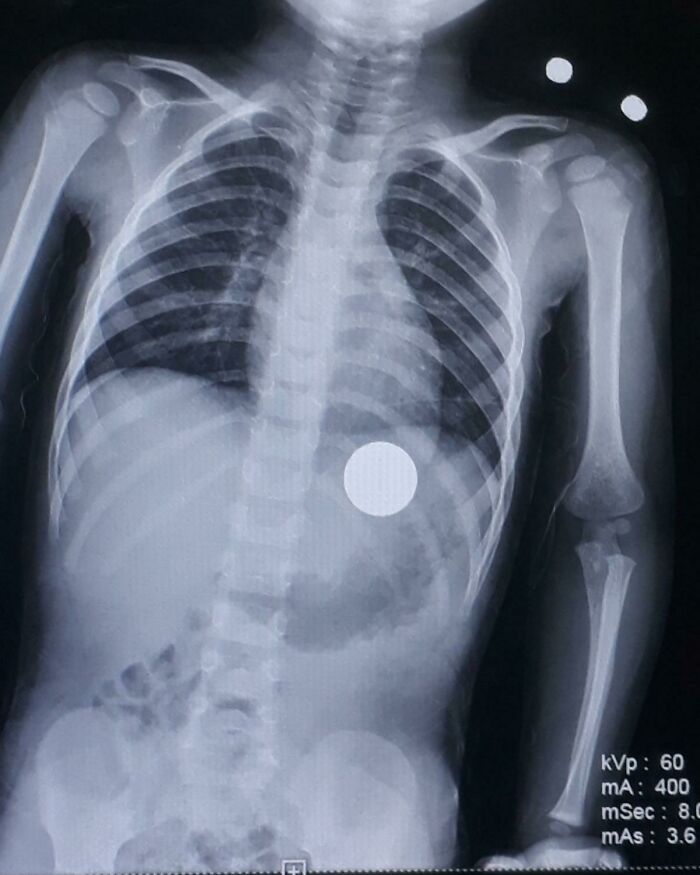

Mężczyzna kompulsywnie zjadał monety — w przewodzie pokarmowym znaleźliśmy około 7 dolarów drobnych. Umarł, dławiąc się ćwierćdolarówką. Trochę zabawne jest myśleć, że zmarł robiąc to, co lubił.